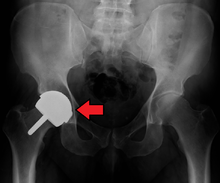

Hip replacement is a surgical procedure in which the hip joint is replaced by a prosthetic implant. Hip replacement surgery can be performed as a total replacement or a hemi (half) replacement. Such joint replacement orthopaedic surgery is generally conducted to relieve arthritis pain or in some hip fractures. A total hip replacement (total hip arthroplasty) consists of replacing both the acetabulum and the femoral head while hemiarthroplasty generally only replaces the femoral head. Hip replacement is currently the most common orthopaedic operation, though patient satisfaction short- and long-term varies widely. The average cost of a total hip replacement in 2012 was $40,364 in the United States, and about $7,700 to $12,000 in most European countries.[1]